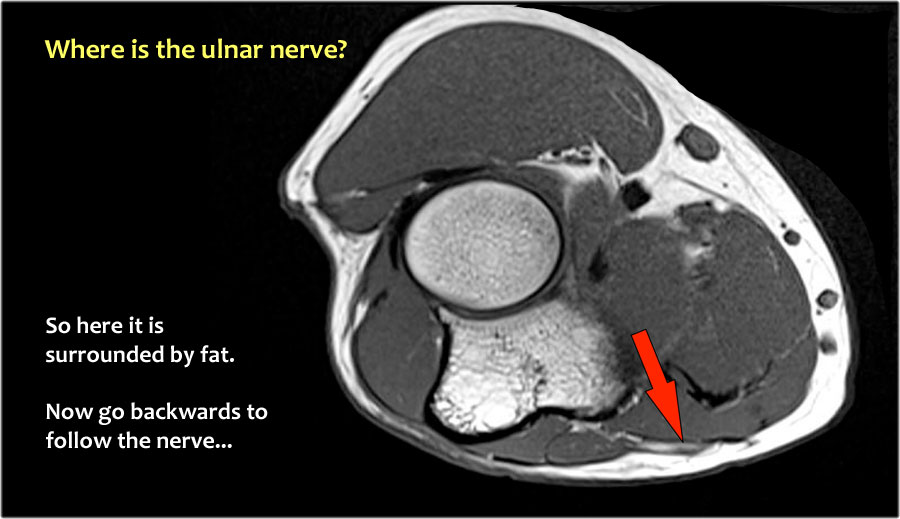

Một cách để thực hiện là đi theo các cấu trúc về phía xa cho đến khi tìm thấy dây thần kinh trụ ở phía xa tại vị trí bình thường của nó ở vùng cẳng tay gần được bao quanh bởi mô mỡ.

Sau đó khi bạn theo dõi nó về phía gần, bạn sẽ nhận thấy rằng đây là một trường hợp chuyển vị dưới da.